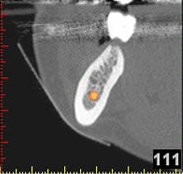

Auf Basis einer computertomografischen (CT-) Kieferaufnahme ist eine dreidimensionale Darstellung der Knochen möglich. Der Zahnarzt kann dann am Computerbildschirm die Knochenqualität (z. B. Knochendichte) beurteilen und die optimale Position der Implantate im Vorfeld planen. Durch Verwendung spezieller Röntgenschablonen lässt sich auch die erwünschte Zahnstellung in die Planung einbeziehen. Die Simulation der OP erlaubt, das zu erwartende Ergebnis mit größtmöglicher Sicherheit vorherzusagen und dem Patienten am Bildschirm zu veranschaulichen.

(siehe Bild 3 und 4).